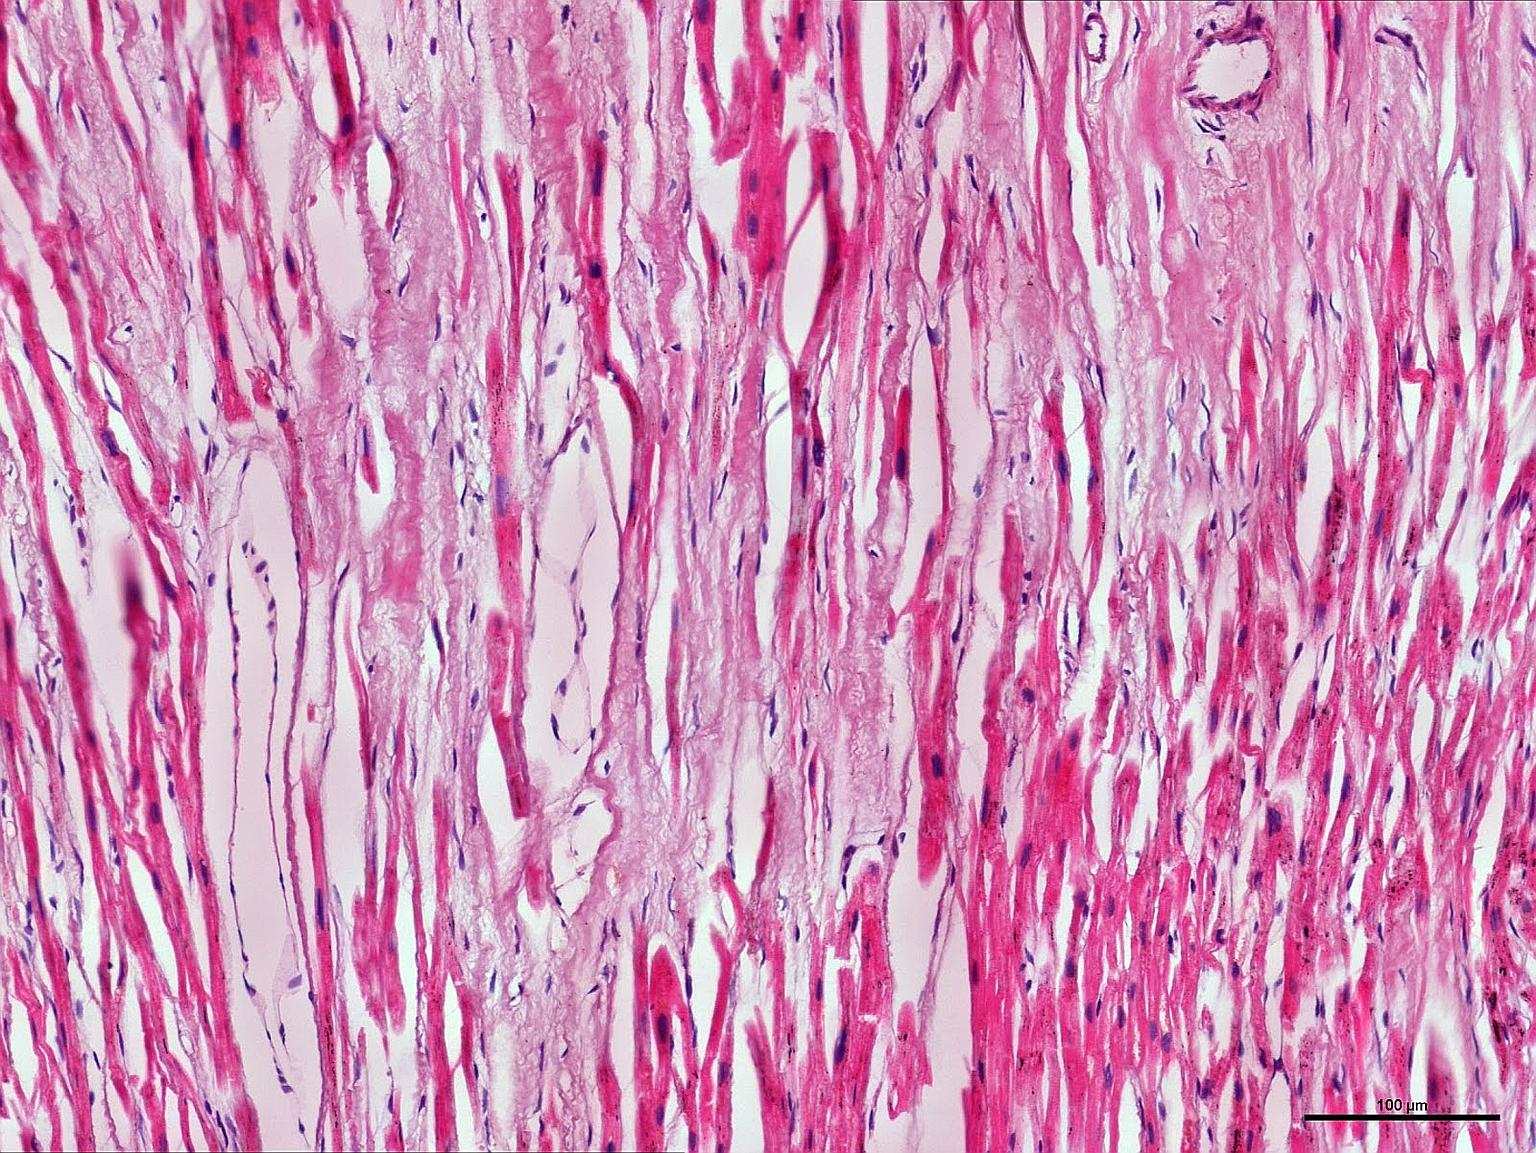

A cross-sectional view of the heart muscle. The NUS team's gene map took about five years to develop.

PHOTO: NUS YONG LOO LIN SCHOOL OF MEDICINE

The map took about five years to develop, and the researchers studied tissues from 36 healthy hearts and 34 failing hearts to map out the genes and switches.